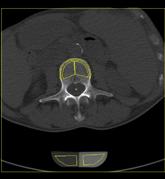

Das Klinikum Ludwigshafen verfügt über einen Kardio-CT der neuesten Generation: Das 128-Zeilen-Gerät ermöglicht eine äußerst präzise Untersuchungsmethode zur Darstellung der Herzkranzgefäße des schlagenden Herzens.

Die koronare Herzerkrankung (KHK) ist eine der häufigsten Erkrankungen in der westlichen Welt. Bei dieser Erkrankung führen Kalkablagerungen an der Gefäßwand (Arteriosklerose) zur Verengung des betroffenen Gefäßes. Diese Engstellen (Stenosen) vermindern die Blutversorgung des Herzmuskels. Kommt es mit dem Fortschreiten der KHK zum Gefäßverschluss, entsteht ein Herzinfarkt.

Die Computertomografie des Herzens (Kardio-CT) ist eine Methode, die frühen Stadien der KHK zu erkennen, bzw. eine KHK mit an Sicherheit grenzender Wahrscheinlichkeit ausschließen zu können.

- Bestimmung der Kalklast (sog. Calcium-Score) beim Patienten ohne Symptome, um das Risiko für das Entstehen einer KHK zu bestimmen

Prinzipiell ist die Kardio-CT eine Computertomografie (CT), also eine Röntgenuntersuchung, bei der die Röntgenröhre spiralartig um den Patient rotiert. Das Besondere ist die enorme Leistungsfähigkeit der CT, bei der mehrere, sehr dünne Schichten pro Umdrehung gleichzeitig aufgenommen werden.

In Ludwigshafen verwenden wir einen CT der neuesten Generation der Firma Siemens, mit dem wir 128 Schichten pro Umdrehung aufnehmen. Auf diese Weise lässt sich das gesamte Herz mit nur vier bis fünf Umdrehungen erfassen. Für Sie bedeutet das, dass wir Ihre Herzkranzgefäße in der derzeit bestmöglichen Auflösung und mit geringst möglicher Strahlenbelastung darstellen können.